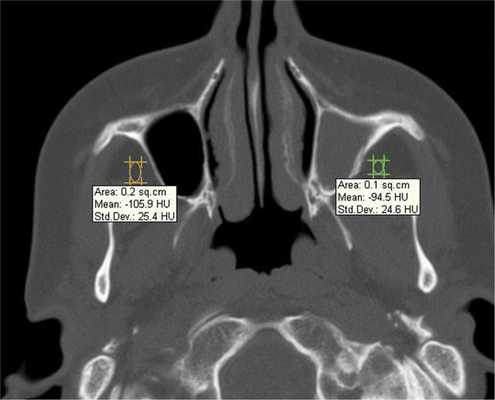

При воспалительных изменениях в ретроантральной жировой клетчатке верхнечелюстной пазухи на РКТ повышаются денситометрические значения ее плотности [10]. При одностороннем процессе отмечается выраженная асимметричность значений плотностей (рис. 4).

Рис. 4. Рентгеновская компьютерная томограмма околоносовых пазух. Аксиальная проекция, костное окно.

Больной Л., 44 года, 15 лет назад терапевтическое лечение 16-го зуба с последующей перепломбировкой; 5 лет назад было осуществлено удаление 16-го зуба. В настоящее время больной обратился за помощью в ЛОР-отделение по поводу давящих болей в верхнечелюстной области справа. Больному была выполнена РКТ верхнечелюстных пазух (рис. 5, а, б), которая показала, что правая пазуха тотально заполнена мягкотканным содержимым и высокоплотным пломбировочным материалом. Отмечается утолщение костных стенок правой верхнечелюстной пазухи и прилежащей ретромаксиллярной клетчатки (–52 HU справа, –86 HU слева)

Рис. 5. Рентгеновская компьютерная томограмма верхнечелюстных пазух. Аксиальная проекция: костное окно (а), мягкотканное окно (б).